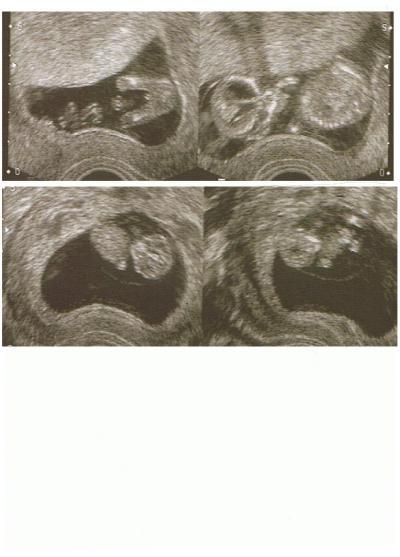

Hallo, hier ist das Bild vom Krümmel,dasoberste war in der 13 Woche und das zweite in der 10 Woche. LG Maria